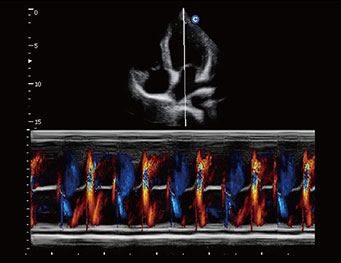

Apical Four Chambers, Color M Mode

TDI, PW Mode